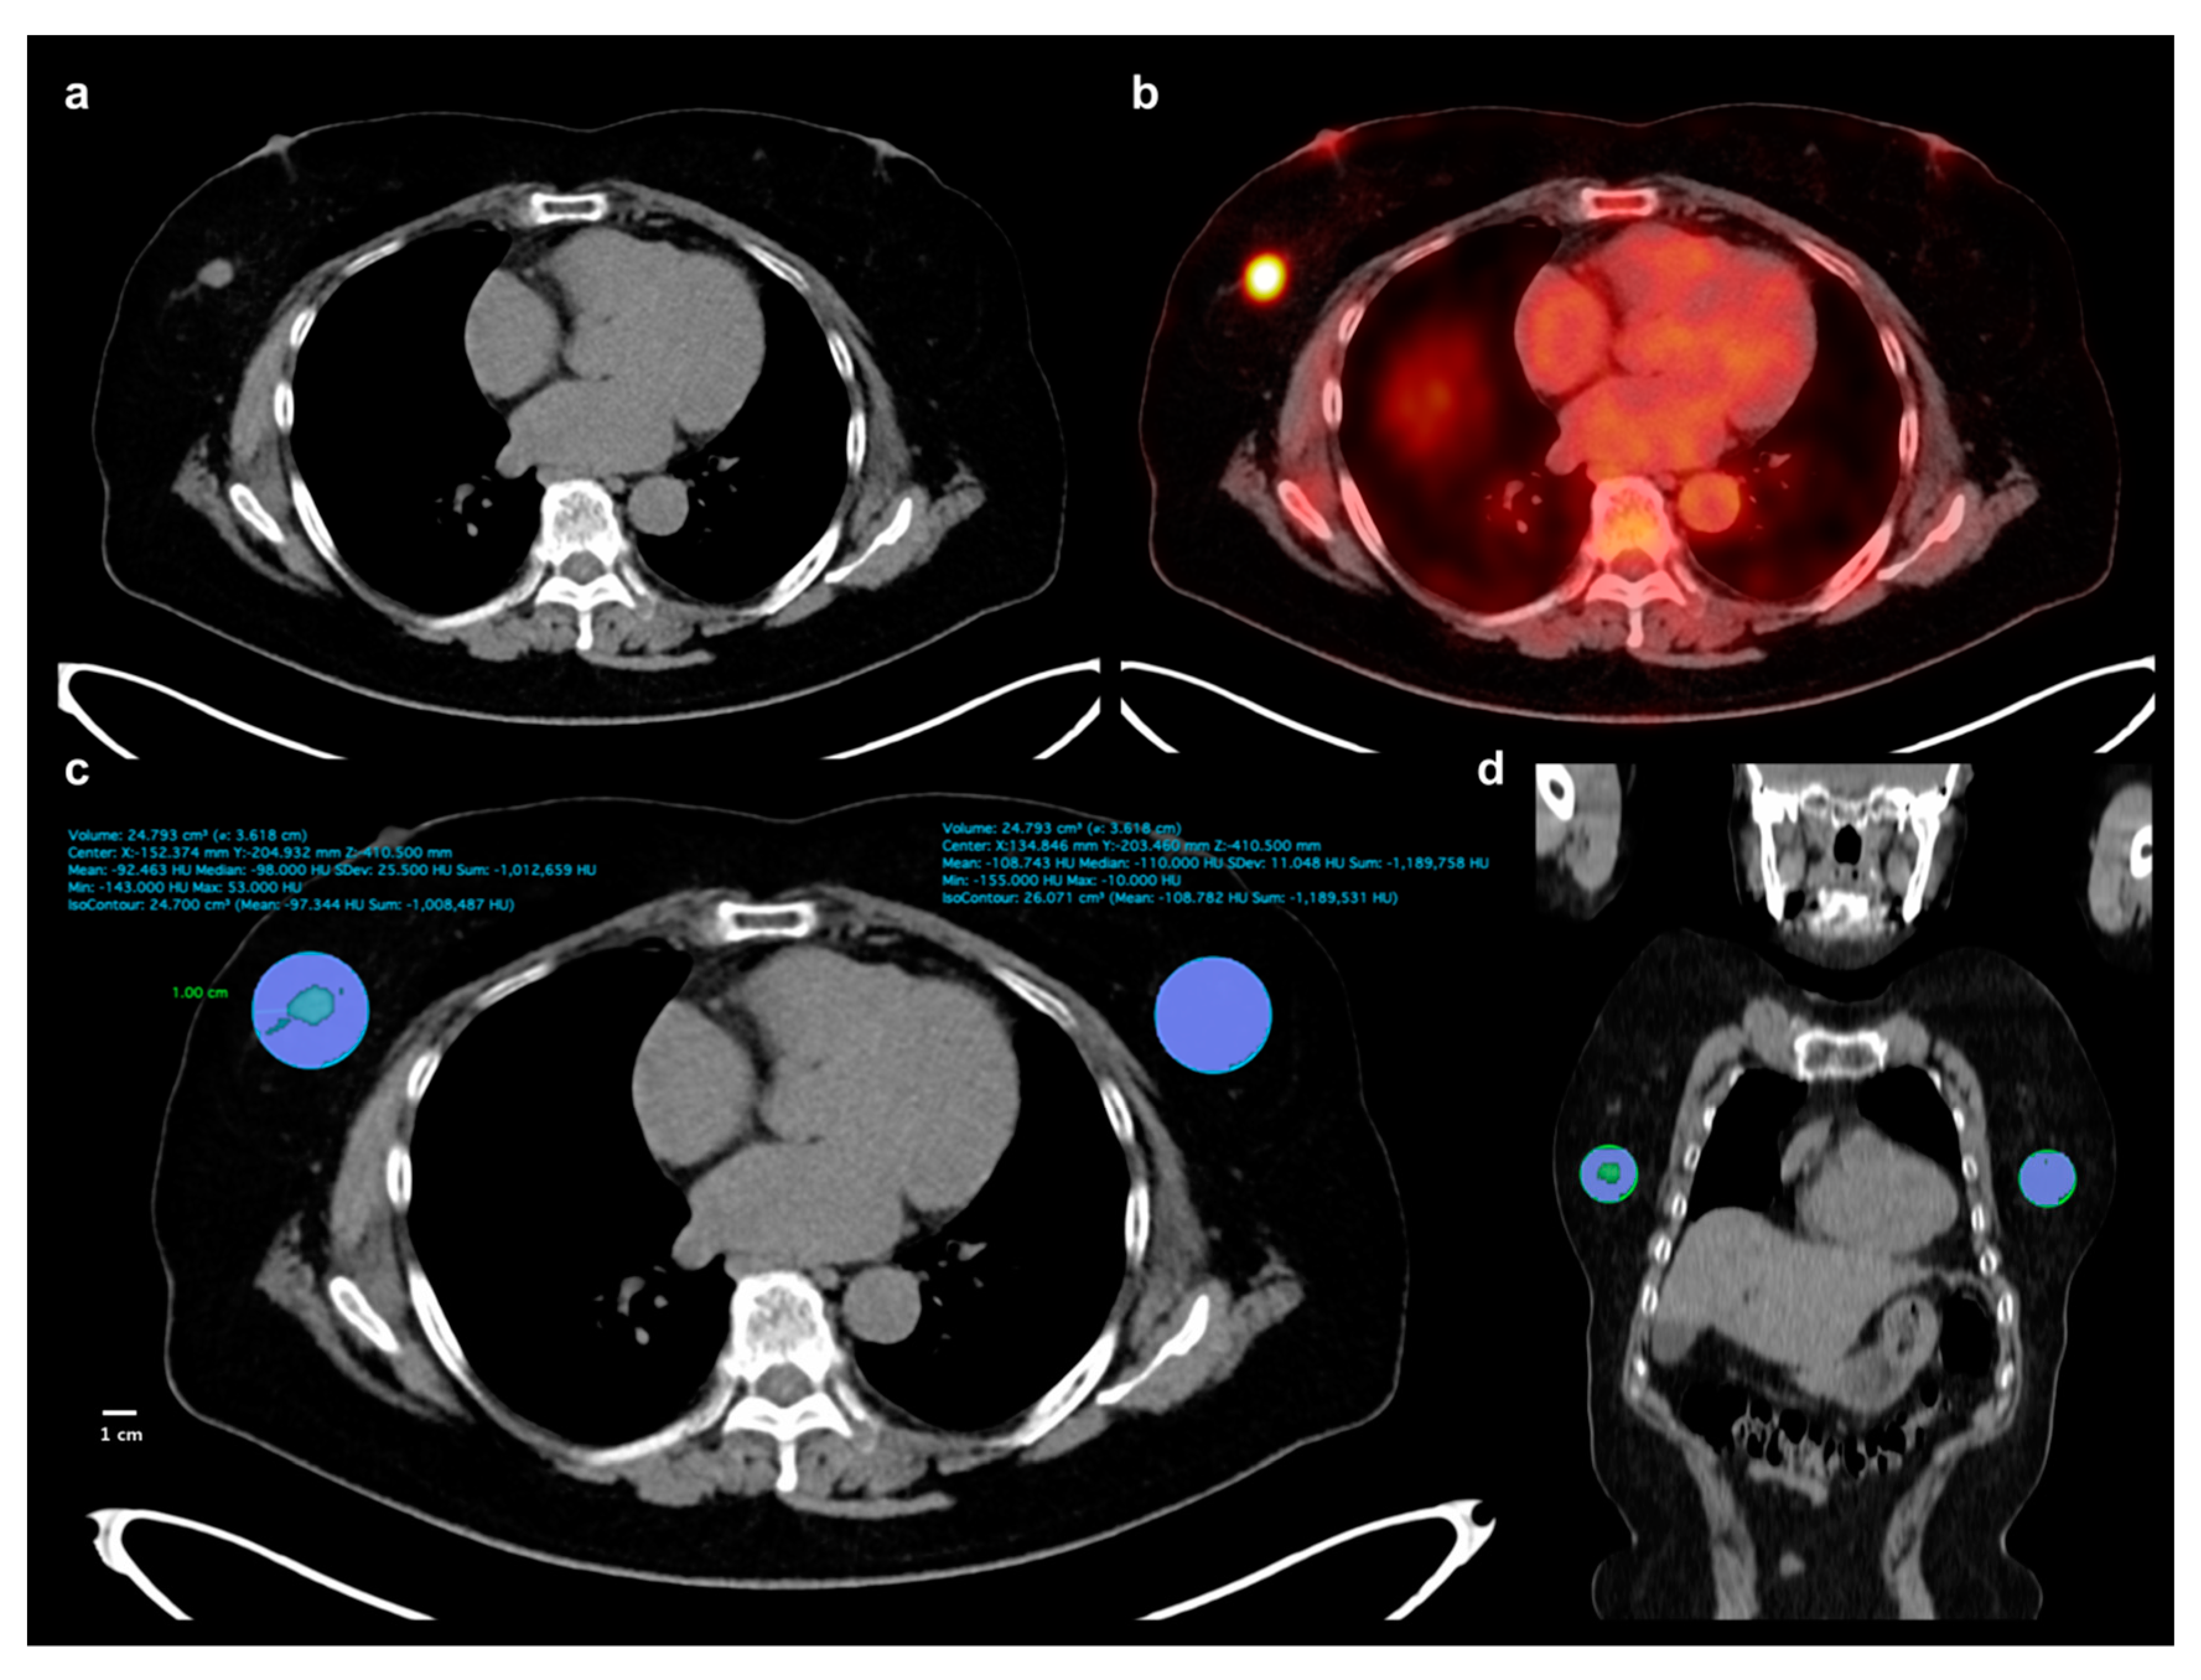

Two expert readers independently reviewed FDG PET/CT images of all patients without knowing clinico-pathological and follow-up results. A United States Food and Drug Administration-approved medical image viewer (OsiriX MD 10.0.3, Pixmeo, Geneva, Switzerland) was used for image analyses. For breast adipose tissue measurement, non-contrast-enhanced CT images of FDG PET/CT were used. A total of four parameters (TAT HU, CAT HU, HU difference, and HU difference %) were measured from breast adipose tissue. We used a 1-cm distance from the tumor margin for defining tumor-adjacent breast adipose tissue. A spheroid-shaped volume-of-interest (VOI) that includes the entire breast cancer lesion and surrounding breast tissue within a 1-cm distance to the tumor margin was manually drawn (Figure 4). Afterwards, another spheroid-shaped VOI of the same size was drawn over the contralateral breast tissue in the same quadrant of the breast tissue (Figure 4). A CT-attenuation range of −200 and −50 HU was used to define breast adipose tissue within VOIs. The mean CT-attenuation value of the area within the CT-attenuation range of breast adipose tissue was measured for each VOI and defined as TAT HU and CAT HU. Using TAT HU and CAT HU, HU difference and HU difference % were calculated as follows: (HU difference) = (TAT HU) − (CAT HU) while (HU difference %) = ((CAT HU) − (TAT HU))/(CAT HU) × 100. Using FDG PET images, we measured two metabolic parameters of primary breast cancer lesion, maximum SUV and MTV. A spheroid-shaped VOI was drawn over the primary cancer lesion on fused PET/CT images including the whole tumor lesion. The maximum SUV of the primary breast cancer lesion was measured. A total volume of voxels that had SUV of 2.50 or greater within VOI was measured and defined as MTV of primary cancer lesion.

Figure 4.

Measurement example of CT-attenuation of tumor-adjacent breast adipose tissue and contralateral breast adipose tissue. A 62-year-old woman underwent FDG PET/CT for staging work-up of right breast cancer, histopathologically confirmed as invasive ductal carcinoma. A mass lesion with intensely increased FDG uptake is observed in outer aspect of right breast, (a,b), showing maximum SUV of 8.44. A spheroid-shaped volume-of-interest that includes peritumoral breast tissue within a 1-cm distance from the tumor margin was manually drawn over the ipsilateral breast tissue, (c,d). Another spheroid-shaped volume-of-interest of the same size was drawn over the contralateral breast tissue in the same quadrant of the breast, (c,d). Within the volume-of-interests drawn in bilateral breast tissues, the area of breast adipose tissue defined as an area with CT-attenuation range between −200 and −50 HU was automatically delineated. Mean CT-attenuation value of breast adipose tissue was measured for each VOI (c): −92.463 HU for tumor-adjacent breast adipose tissue and −108.743 for contralateral breast adipose tissue.